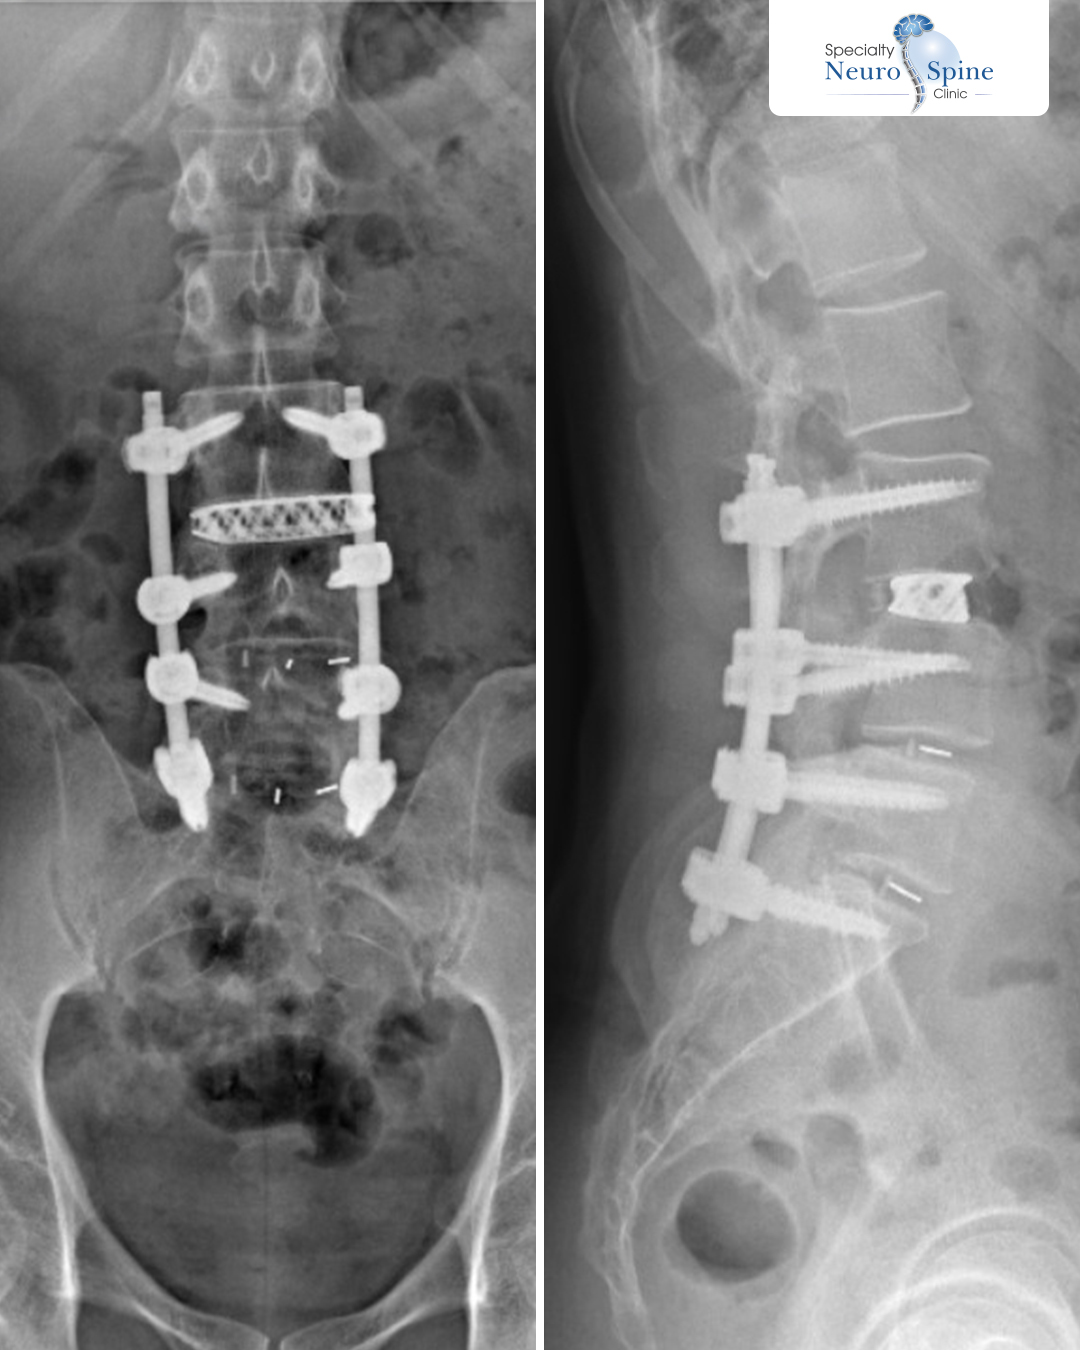

Frontal and lateral X-ray images of our dear patient, Turki (48 years old) from the UAE.

The results demonstrate the success of the Oblique Lumbar Interbody Fusion (OLIF) from the 3rd lumbar vertebra (L3) to the 1st sacral vertebra (S1).

The images show stable vertebral alignment post-fusion and effective nerve decompression achieved through minimally invasive surgical techniques.